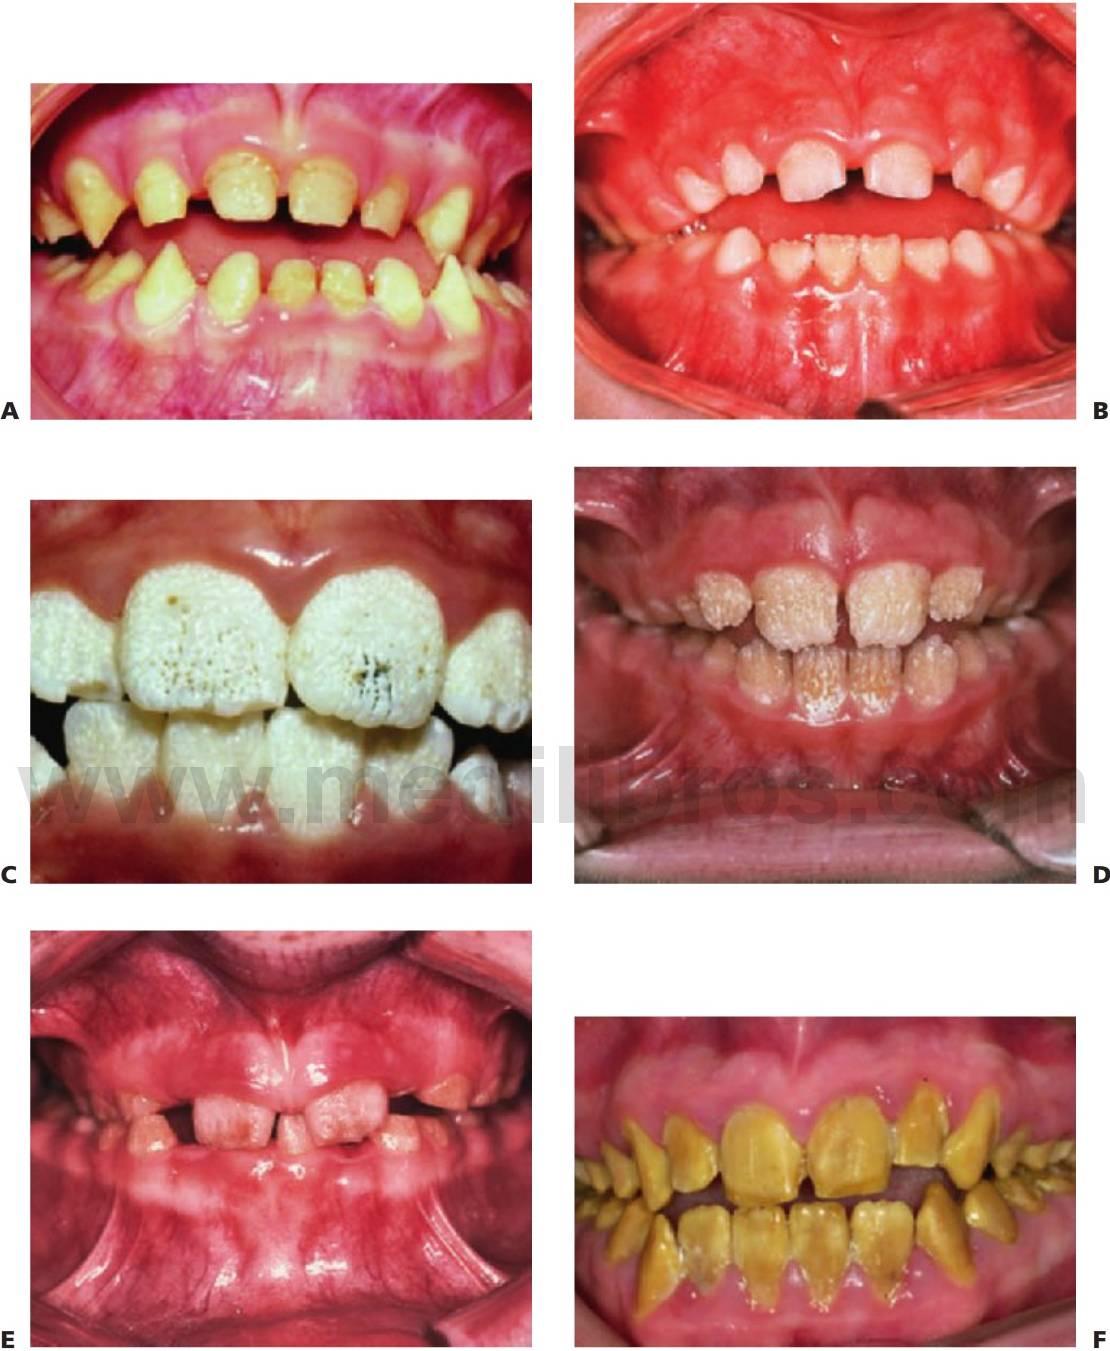

Amelogénesis imperfecta

El término amelogénesis imperfecta (fig. 9.25) suele aplicarse a defectos hereditarios del esmalte que afectan tanto a los dientes temporales como a los permanentes. La definición implica una historia familiar, pero en la práctica parece razonable ampliar esta definición para incluir los casos esporádicos y aquellos otros en los que los defectos del esmalte se asocian a manifestaciones extraorales, como ocurre en algunos síndromes (es decir, hipoplasia dérmica focal o síndrome trico-dento-óseo).

Fenotipos

Los fenotipos oscilan desde el esmalte (fino) marcadamente hipoplásico, uniformes (con espacios entre los dientes) o irregulares (dando lugar a pozos o surcos) hasta los diferentes grados de hipomineralización (esmalte muy mal formado) con alteraciones en su color y traslucidez. En muchos casos, la hipoplasia y la hipomineralización se presentan juntos. El color del esmalte refleja con claridad el grado de hipomineralización del mismo: cuanto más oscuro se presente el tono, más grave será la desmineralización.

En la amelogénesis imperfecta ligada al cromosoma X, las mujeres presentan franjas ver ticales de esmalte alterado como signo de lyonización (v. hipótesis de Lyon, descrita en este mismo capítulo). Pueden ser surcos verticales (debido a la hipoplasia) y/o bandas verticales de esmalte con el color o lucidez alterados (debido a la hipomineralización), o bien una combinación de ambos. En estas familias no existirá transmisión de varón a varón, pero las mujeres heterocigóticas pueden transmitir el rasgo a niños del mismo sexo.

En algunos pacientes afectados por amelogénesis imperfecta, los dientes no llegan a erupcionar, se cree que debido a una alteración del órgano del esmalte y sufren una reabsorción de sus coronas. En algunos casos (más del 50%) se observa una mordida abierta esquelética anterior.

Formas predominantes/exclusivas de la hipoplasia dental

- Esmalte fino.

- Ausencia de punto de contacto entre los dientes.

- El esmalte puede ser rugoso, liso o con pozos repartidos al azar.

- Las mujeres heterocigóticas con amelogénesis imperfecta ligada al cromosoma X manifiestan lyonización (v. antes) con franjas verticales de esmalte normal y anómalo.

- La erupción de los dientes se retrasa.

- Los dientes que no han erupcionado pueden reabsorberse.

- Mordida abierta anterior asociada en aproximadamente el 50% de los casos.

- En el plano radiográfico, puede resultar difícil distinguir el esmalte de la dentina si aquél es demasiado fino.

Formas predominantes/exclusivas de hipomineralización del esmalte

- El esmalte tiene un espesor normal, al menos inicialmente.

- El color es amarillo o pardo.

- El esmalte es más blando de lo normal, tiende a astillarse y se puede atravesar con un explorador. En los casos muy hipomineralizados, se puede arañar el esmalte con una cureta.

- Los dientes pueden erupcionar con un espesor normal, pero el esmalte se pierde pronto, dejando al descubierto una dentina rugosa y muy sensible.

- Se forman grandes masas de cálculo supragingival.

- En el plano radiográfico, resulta difícil distinguir el esmalte de la dentina debido al menor grado de mineralización del esmalte.

- Los dientes que no han erupcionado pueden reabsorberse, y se debe observar esta reabsorción mediante radiografías.